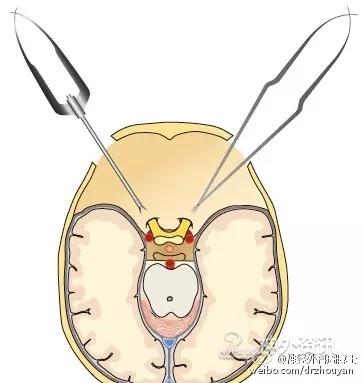

从神经外科出现开始,直至现在——开颅需要花费数小时——这是事实,多数人认为这也是天经地义的。这是因为多数神经外科医生普遍采用的仍是大范围、广泛的开颅方法。这也同时造成了另外一个事实:脑组织表面遭受非生理学环境的损伤,如空气、冲洗、贴敷材料或是脑压板的压迫力。我们需要特别注意,这些脑表面的微损伤很有可能就是术后癫痫发生的原因。这也同时解释了“为什么开颅手术的病人术后常规都要使用抗癫痫药物进行预防性治疗?”这里,我们先进行一个比较,一方是keyhole开颅方法,骨瓣直径约2cm;另一方是传统的广泛大范围开颅方法,骨瓣直径约8cm。比较的内容就是脑皮层暴露的范围和外科创伤程度。比较的方法是利用公式计算:面积=π×r2(r为骨瓣的半径)。结果是:传统的开颅方法脑表面暴露的面积是π×r2=4cm2×π=50.27cm2;keyhole开颅方法则为π×r2=1cm2×π=3.14cm2。显而易见,keyhole可以显著的减低脑皮层表面的损伤。当然,并不是所有的病例都适合,需要具体问题具体分析。

同时,keyhole开颅方法还可大大减少脑组织的牵拉。1934年,Eugene M. Landis阐述了毛细血管血压的生理范围。自此之后,大量的实验和临床研究均表明,术中过度脑牵拉一定会导致明显的脑组织损伤,并可产生永久性神经功能障碍。这个研究结果目前已获广泛认同。为了能使牵拉脑组织的程度降至最小,医生们想了很多办法,比如使用特殊的麻醉技术以降低脑组织的张力,发明特殊的脑牵拉设备,以及采用特殊手术体位等。但是,最好的牵拉技术就是“不牵拉”。仔细选择一个合适的、侵袭性小的手术入路,并使脑组织暴露和牵拉都降至最小,就可以显著降低颅内结构的损伤几率。

A. 标准的大范围开颅,暴露术野深部病变的视角呈漏斗型; B. 这种传统的大范围开颅方法可以被视为若干keyhole手术入路的整合;C. 只要选择正确的小骨窗路径,手术视角呈扇形扩大。路径越短,手术视角越窄;而路径越长(术野深部病变),手术视角则越宽。这种路径选择方法,有时还可同时处理对侧的病变。